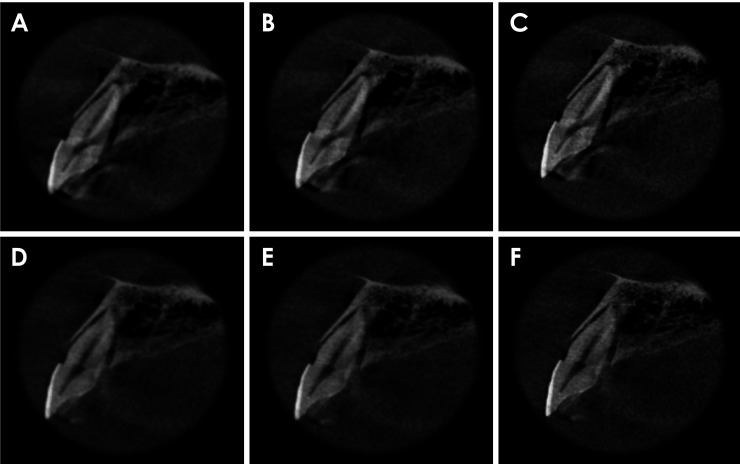

目的:本研究探讨了减少金属伪影(MAR)、应用锐化滤波器及其组合对锥形束计算机断层扫描(CBCT)检查中氧化锆种植体邻近牙齿水平根折(HRF)诊断的影响:将 19 颗单根牙齿(9 颗有 HRF,10 颗没有 HRF)分别置于干燥人类上颌骨的右中切牙牙槽窝中。每颗牙齿旁边都植入了一颗氧化锆种植体。成像使用 OP300 Maxio CBCT(Instrumentarium,芬兰图苏拉)设备进行,设置如下:8 mA 电流、两种 MAR 模式(启用和禁用)、5×5 cm 视场、0.085 mm 像素大小和 90 kVp 峰值电压。四名口腔颌面部放射科医生在两种 MAR 条件下和 3 种锐化滤镜应用水平(无、锐化 1× 和锐化 2×)下独立评估 CBCT 扫描。诊断指标通过双向方差分析(α=5%)进行计算和比较。加权卡帕检验用于评估 HRF 诊断中检查者内部和检查者之间的可靠性:结果:MAR工具的激活、锐化滤波器的使用及其组合对HRF诊断的接收者工作特征曲线下面积、灵敏度或特异性没有显著影响(P>0.05)。检查者内部和检查者之间的一致性从一般到相当可观不等:结论:氧化锆种植体邻近牙齿的 HRF 诊断不受 MAR 激活、锐化过滤器应用或这些工具组合的影响。

Materials and methods: Nineteen single-rooted teeth (9 with HRF and 10 without) were individually positioned in the right central incisor socket of a dry human maxilla. A zirconia implant was placed adjacent to each tooth. Imaging was performed using an OP300 Maxio CBCT (Instrumentarium, Tuusula, Finland) unit with the following settings: a current of 8 mA, both MAR modes (enabled and disabled), a 5×5 cm field of view, a voxel size of 0.085 mm, and a peak kilovoltage of 90 kVp. Four oral and maxillofacial radiologists independently evaluated the CBCT scans under both MAR conditions and across 3 levels of sharpening filter application (none, Sharpen 1×, and Sharpen 2×). Diagnostic metrics were calculated and compared using 2-way analysis of variance (α=5%). The weighted kappa test was used to assess intra- and inter-examiner reliability in the diagnosis of HRF.